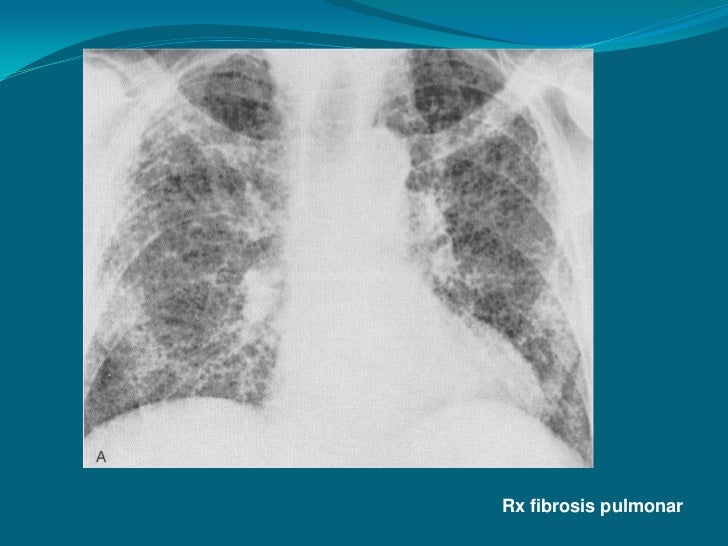

Mujer de 80 años con importante fibrosis pulmonar en rx de tórax el electrocardiograma con importante crecimiento y sibrecarga del ventrículo derecho por.